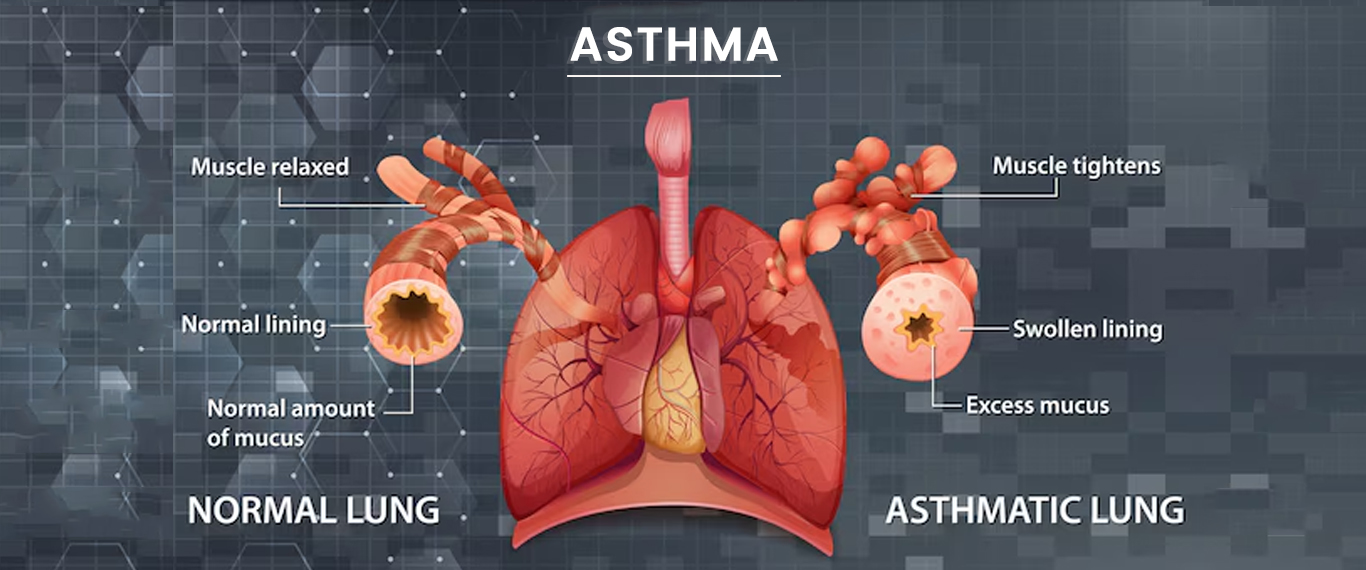

Asthma

Asthma is a chronic respiratory condition causing airway inflammation, leading to difficulty breathing, wheezing, coughing, and chest tightness.